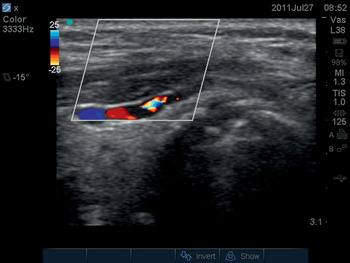

Heart: cardiac arrest and shock (focused echo)

A formal echocardiograph scan systematically inspects all structures of the heart, aiming to diagnose any abnormality found. This is not the role of a “focused scan.” The intensive care patient typically has a life-threatening cardiorespiratory problem of uncertain cause. Clinical examination of the patient allows a differential diagnosis to be made, e.g., shock of septicemic or cardiogenic origin. The role of the focused echo is to look for specific ultrasound signs which allow differentiation between these diagnoses. The FEEL [7] and FATE [8] focused echocardiography protocols have been developed for this purpose. They use the apical, subxiphoid, and parasternal short- and long-axis views to answer specific questions about cardiac performance during cardiac arrest or shock. These four views are shown on Videos 6.5a–d.

Shock

Focused echocardiography readily distinguishes between shock states with high cardiac output and those with low cardiac output. Left ventricular stroke volume can be visualized using the apical, subxiphoid, and parasternal long-axis views. The various shock states appear as follows:

Cardiogenic shock: very poor left ventricle contractility.

Obstructive shock: the appearances of cardiac tamponade and tension pneumothorax are described in the section on ‘Cardiac arrest’ under ‘Circulation’.

Septic, anaphylactic, and neurogenic shock: the left ventricle empties supramaximally and contractility is normal.